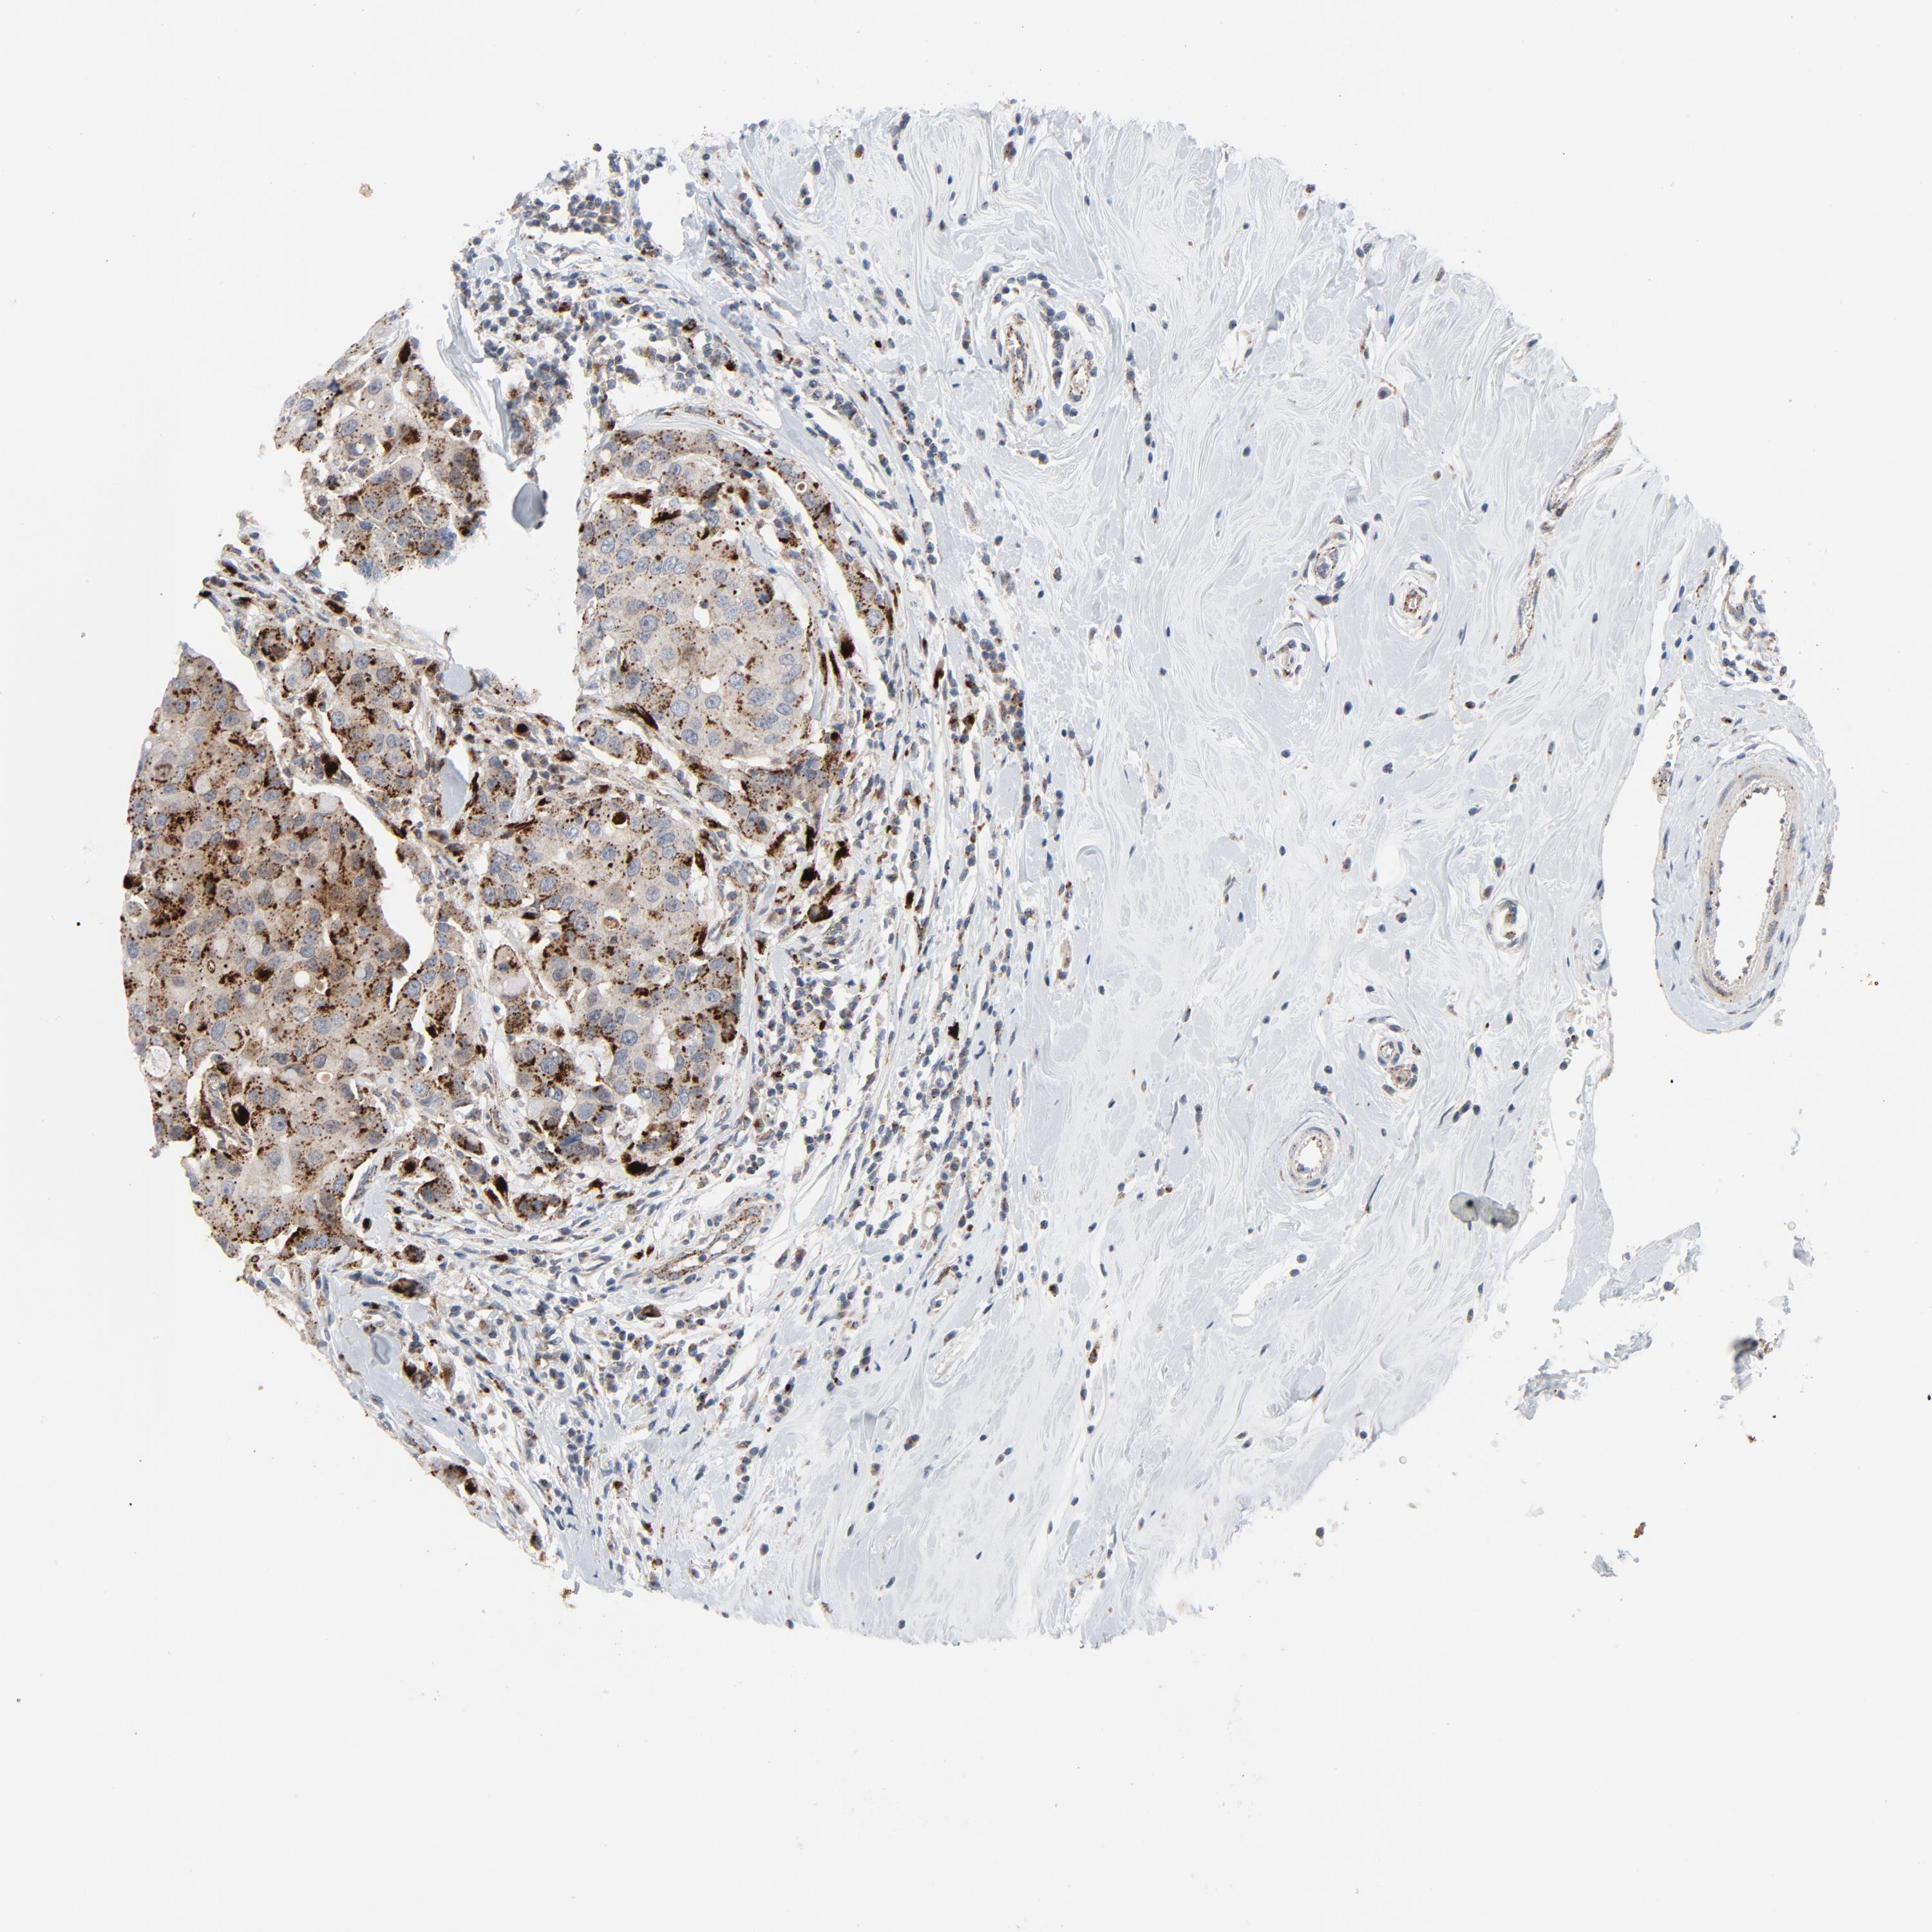

BRCA TCGA BRCA VALIDATION PROTEIN EXPRESSION